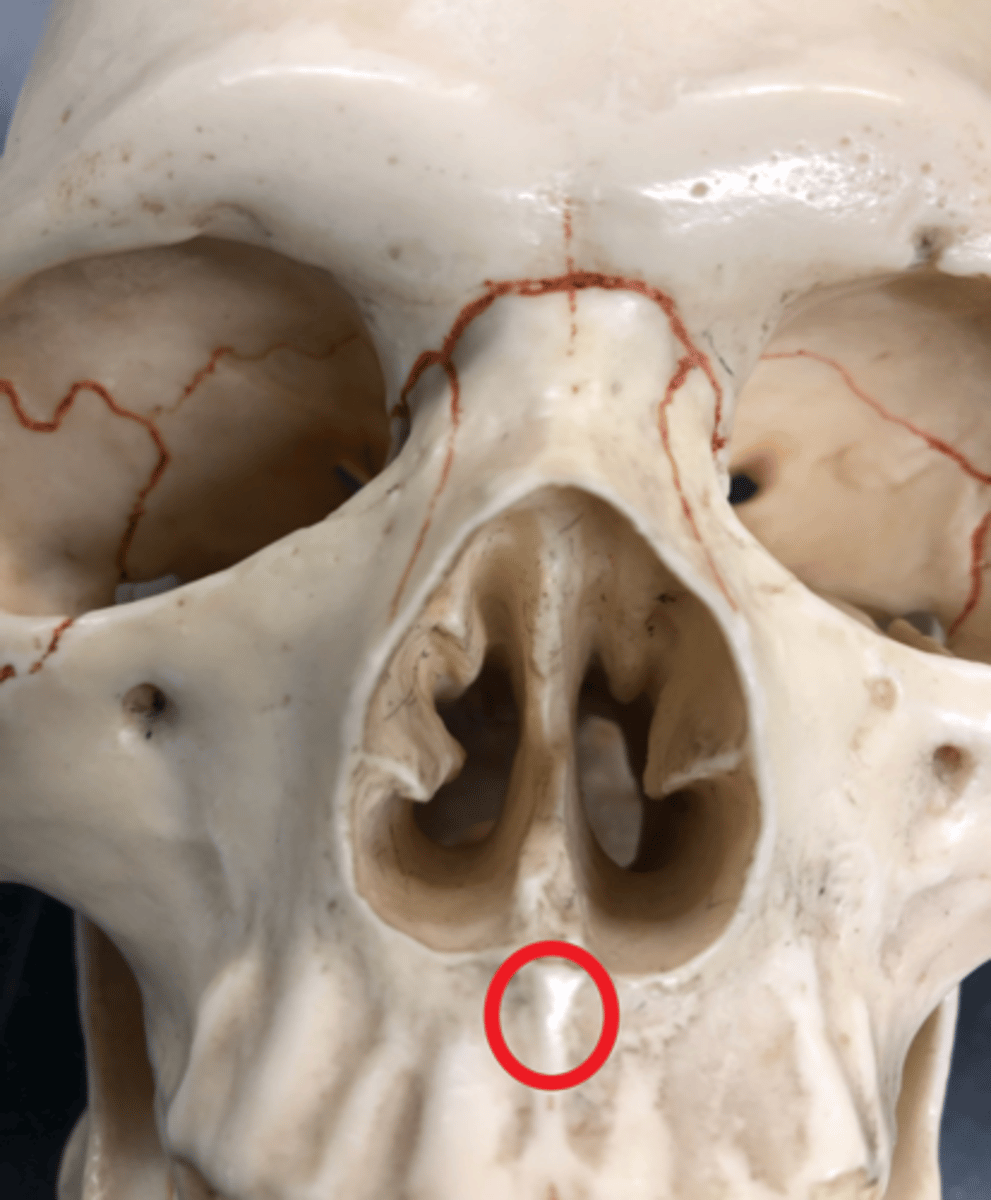

Name this bony landmark.

acanthion